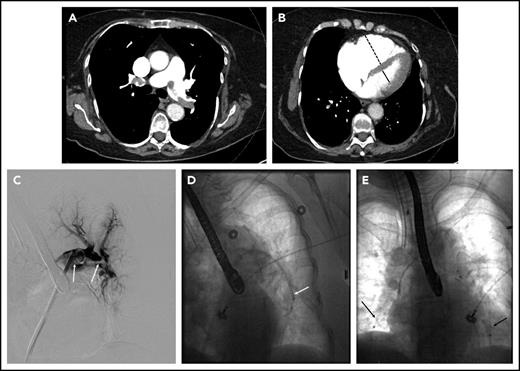

A 78-year-old woman with hypertension, hyperlipidemia, and chronic obstructive pulmonary disease presented to the emergency room with 4 hours of chest pain associated with lightheadedness and diaphoresis. She had an oxygen saturation of 86% on room air and a systolic blood pressure of 80 mmHg. Her oxygen saturation improved to 98% on 2 L of oxygen by nasal cannula. Initial labs were notable for a troponin of 0.44 ng/mL (normal <0.04 ng/mL). Electrocardiography was normal. The d-dimer was 8820 ng/mL, prompting CT angiography of the pulmonary arteries, which revealed multiple bilateral PE in the main pulmonary arteries (Figure 2A), with evidence of right heart dilation (Figure 2B) and strain on transthoracic echocardiography. The patient was started on UFH and transferred to the intensive care unit (ICU) for further management. Lower extremity ultrasound revealed residual acute DVT in the right popliteal and tibial veins. The PERT was activated, and the initial consensus was to not escalate therapy beyond anticoagulation because she had stabilized. However, 12 hours after admission to the ICU, she developed hypotension (systolic blood pressure of 78 mmHg) and was started on vasopressors. The PERT was alerted to this new development, and the decision was made to proceed with catheter-directed therapy.

Massive pulmonary embolism in patient 3. (A) Axial CT image demonstrating thrombus in the right and left main pulmonary arteries. (B) Axial CT image through the heart demonstrating an enlarged RV (dashed line) to LV (solid line) ratio. (C) Thrombus on pulmonary angiography (arrows), extending from the left main pulmonary artery into the left lower-lobe pulmonary artery. (D) Indigo aspiration device (arrow) within the left lower-lobe pulmonary artery. (E) Placement of bilateral CDT infusion catheters (arrows).

Because of the patient’s instability and hypoxia, general anesthesia with endotracheal intubation was performed by a cardiac anesthesiologist. Pulmonary angiography was performed, showing the bulk of the thrombus in the left lower-lobe pulmonary artery (Figure 2C). The Indigo CAT 8 aspiration device (Penumbra, Inc., Alameda, CA) was used in an attempt to rapidly debulk thrombus (Figure 2D). Bilateral multisidehole infusion catheters were then positioned in each pulmonary artery (Figure 2E), and 0.5 mg rt-PA/catheter/h was initiated, with UFH infusion targeted to PTT less than 2 times the institutional norm. Additionally, a retrievable inferior vena cava (IVC) filter was placed at the time of the procedure. After a total dose of 12 mg, the patient was noted to have significant oozing from the catheter site, so thrombolytic infusion was halted. Her blood pressure was normal, and she was no longer requiring vasopressor support. The catheters and sheaths were removed at the bedside. Therapeutic-level UFH was resumed. The patient was discharged 2 days later on anticoagulation. The IVC filter was removed percutaneously 6 weeks later, at which time the patient was doing well with no functional limitations.